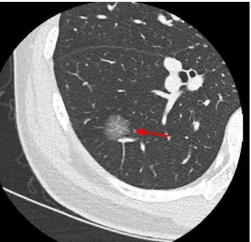

纯磨玻璃结节(类似荔枝果肉)、混合磨玻璃结节(类似荔枝果肉与果核并存)(恶性风险较高)、实性结节(类似荔枝果核)。

纯磨玻璃结节 | 混合磨玻璃结节 | 实性结节 |